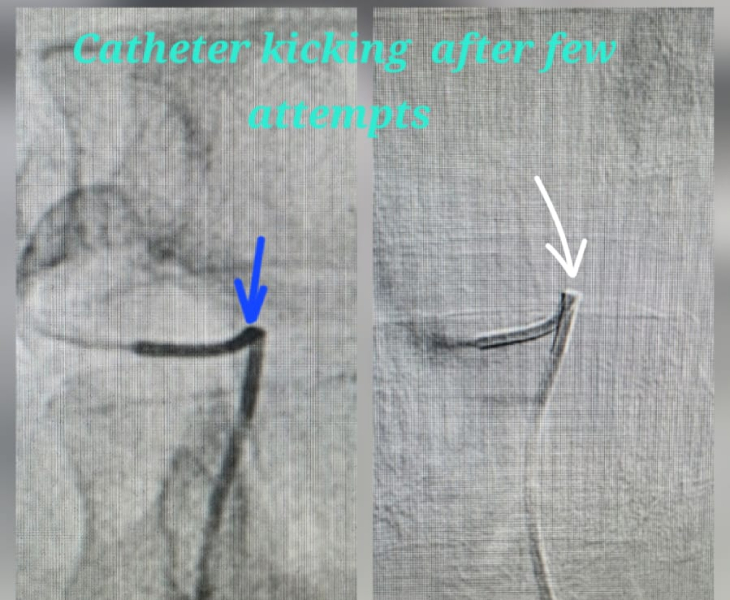

- Super‑selective catheterisation: a microcatheter is advanced into the specific branch feeding the pseudoaneurysm.

- Embolization: coils and/or other embolic agents are deployed to stop blood flow to the pseudoaneurysm.